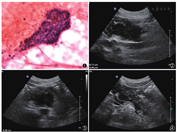

超声内镜检查提示:胰头不规则低回声,内部回声不均匀,与脾静脉关系密切;胰周可见不规则肿大淋巴结。胰头占位穿刺涂片可见淋巴细胞、导管上皮细胞、腺泡细胞及纤维间质碎片,未见瘤细胞(图1)。胰腺超声检查可见胰腺头体交界处6.1 cm×5.3 cm×4.4 cm低回声区(图2,图3),形态不规则,边界不清,彩色多普勒未见明确异常血流信号;该低回声区将肠系膜上动脉包绕于内,管腔略细,血流通畅。余胰腺腺体回声不均伴钙化及胰管稍宽(图4),脾静脉闭塞。

超声造影示:胰头低回声于动、静脉期均呈同步增强及减退(图5,图6),考虑炎性病变可能性大。